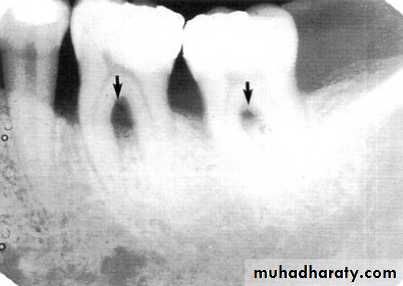

Vertical osseous defects can be divided into two primary types: Interproximal crater is a two-walled, trough like depression

that forms in the crest of the interdental bone between adjacent teeth.

The Infrabony defect is a vertical deformity within bone that extends apically along the root from the alveolar crest.

Interproximal crater

Often infrabony defects are difficult or impossible to recognize on a radiograph because one or both of the cortical bony plates remain superimposed with the defect.

Clinical and surgical inspections are the best means of determining the number of remaining

bony walls.